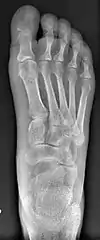

Normal foot skeleton

Fig 1a: Normal foot skeleton

First metatarsal bone has moved aside

Fig. 1b: First metatarsal bone has moved aside

Primus varus deformity is the leaning of the first metatarsal bone away from the second metatarsal and towards the opposite foot (Fig. 1). As it leans over, its head sticks out to form the bunion bump and it also widens the forefoot to cause shoes feeling too tight. Thus when bunion pain becomes unmanageable, surgical correction is to narrow the forefoot by repositioning of the first metatarsal head back to its normal position. This can be done by osteotomy (bone-breaking), soft tissue (non-osteotomy) or fusion techniques.